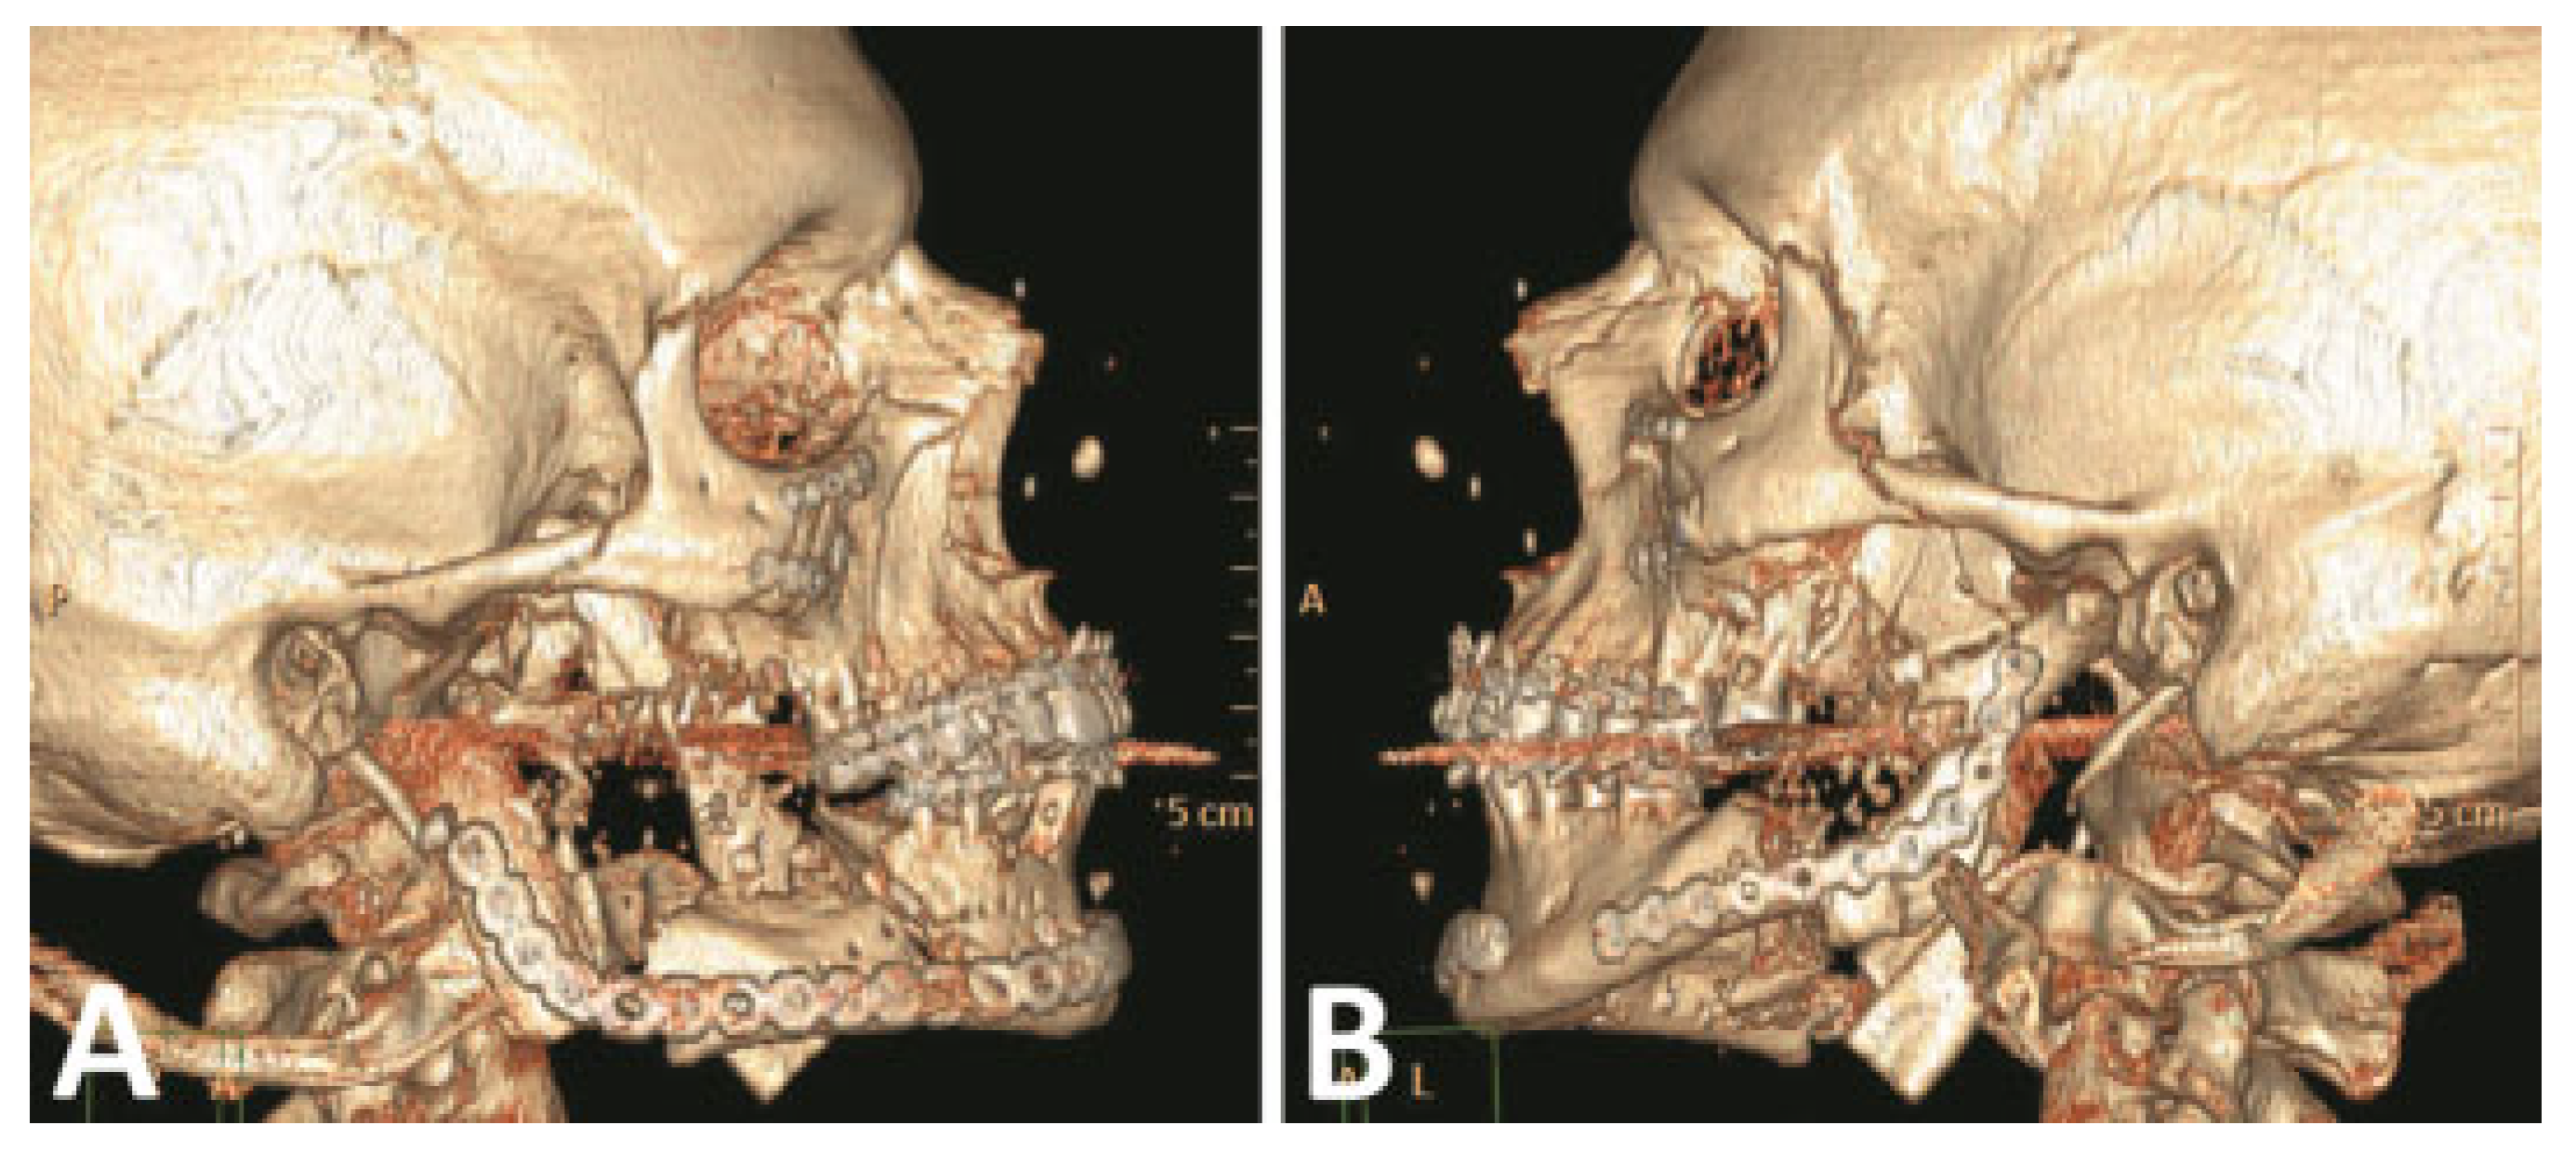

The comminuted left condyle and body fractures were re- paired with 2.0-mm reconstruction plates (Figure 5). A right cheek wound was closed in layers after debridement and placement of a drain.

Figure 5.

(A,B) Primary fracture reconstruction; comminuted right condyle debridement and reconstructed with immediate costochondral graft. (Images are courtesy of Colonel Robert Hale.).